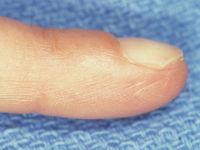

| Case 1. This patient presented with a progressive index finger nail deformity years after an open crush injury of that fingertip. |